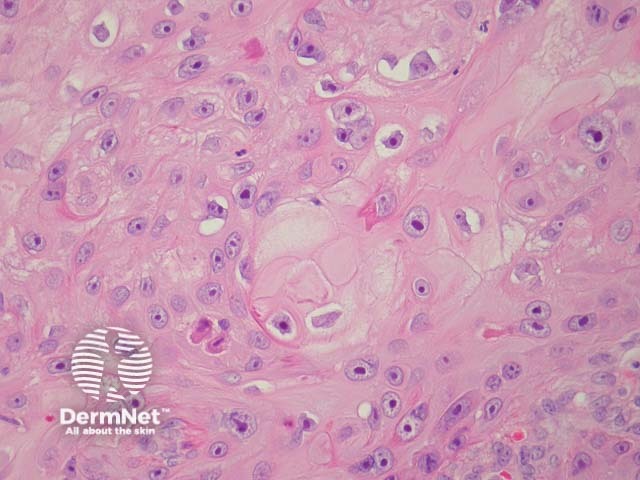

Typical SCC has nests of squamous epithelial cells arising from the epidermis and extending into the dermis (figure 1). The malignant cells are often large with abundant eosinophilic cytoplasm and a large, often vesicular, nucleus. Variable keratinisation (keratin pearls etc) is present (figure 2).

Figure 2